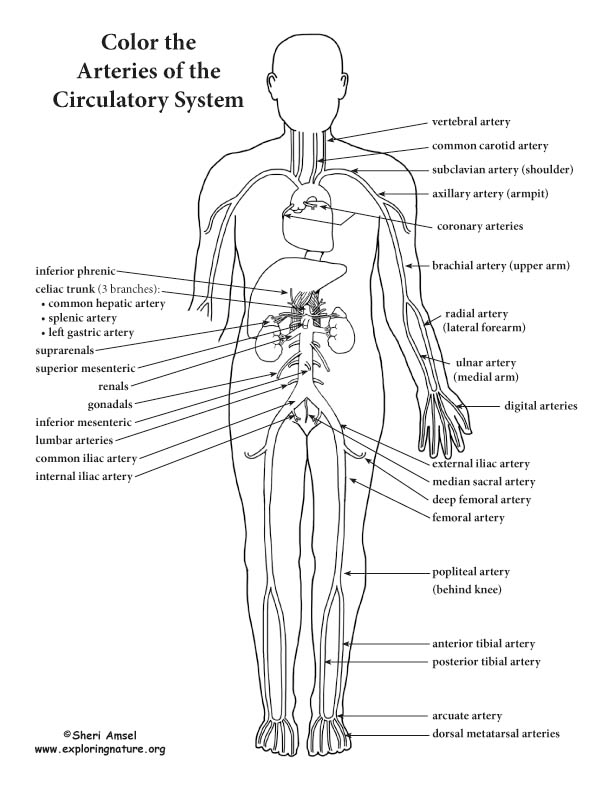

Anatomy and Physiology Blood Vessels Worksheet

Anatomy and Physiology Blood Vessels Worksheet

For a fun way to enhance discovering regarding the human body, you can make use of Anatomy and Physiology Blood Vessels Worksheet. Some of them have labels to make it easy to identify parts of the body.

Some of the human body worksheets are offered for homeschooling. You can also utilize these worksheets for scientific research lessons.